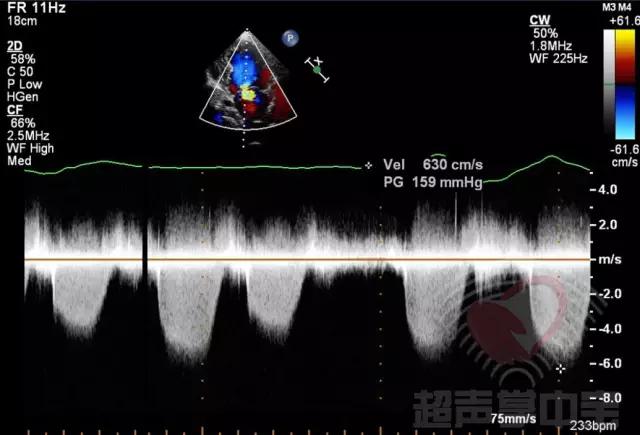

经典病例▏二尖瓣囊肿中竟然全是血液? 图8:CW于囊状物内探及收缩期负向高速湍流,流速6.3m/s,压差159mmHg

经典病例▏二尖瓣囊肿中竟然全是血液? 动态图7:CDFI:显示主动脉瓣中度反流,二尖瓣轻度反流,二尖瓣前叶附着的囊状物内收缩期充满花彩血流